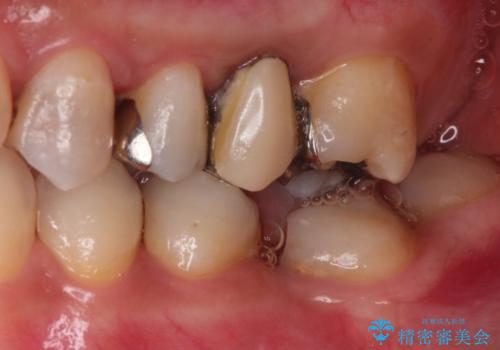

- 歯医者が怖くて悪い歯をそのままにしてしまった、悪いところを治したいとのことで来院されました。

虫歯の歯や、歯を抜いてしまったところをそのまま放置していたことにより、歯並びも悪くなっていました。

矯正をはじめ、根の治療・インプラント・セラミックによる全体治療を提案させていただき、治療をしていくこととなりました。